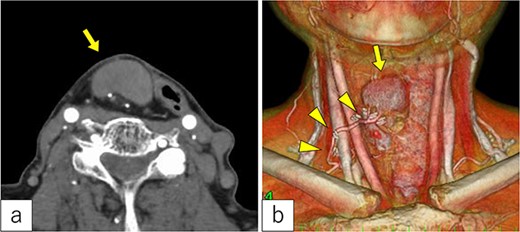

Three years post-TOVS, a mass was noted in the anterior neck (Fig. 1). Computed tomography (CT) revealed lymphadenopathy in the mesenteric lymph node of the transferred jejunal flap, involving the flap’s vascular pedicle (Fig. 2). Ultrasonography-guided fine-needle aspiration cytology revealed atypical nuclei compatible with SCC metastasis.

Radiological findings. (a) Computed tomography revealed a tumor under the cervical flap (arrow). (b) The tumor involved the vascular pedicle of the jejunal flap (arrowhead).